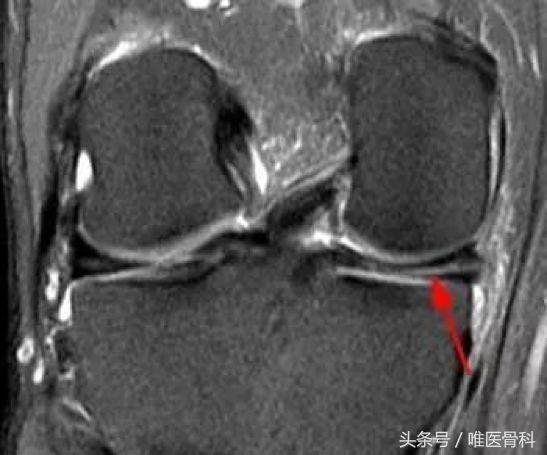

一般医生根据病史,比如膝关节曾经扭伤;病人的症状,比如膝关节内有弹响,走路时有交锁感;体格检查同时结合影像学检查,可以得出比较准确的诊断。半月板损伤最可靠的影像学诊断方法是磁共振检查,虽然价格有点贵,但却是必须的。

因为半月板的很大一部分是没有血液供应的,有比较高的概率无法自行愈合,这个时候就需要手术干预。现在半月板的手术都是通过关节镜进行治疗的,这是一种微创的治疗方式,通常只需要两个1cm左右的切口就可以完成。根据半月板损伤的类型和程度,可采取半月板成形术或者半月板缝合术进行治疗。